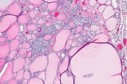

Figure 6.MEN1 syndrome designating a pancreatic polypetide secreting tumour with benign appearing adenomatous glands14.

Figure 7.MEN1 syndrome denominating a pancreatic neuroendocrine neoplasm with accumulation of benign, adenomatous glands15.